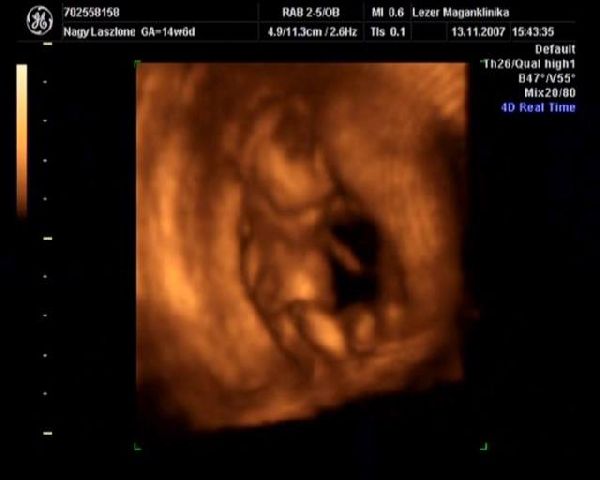

Zsebi, mindig elfelejtem írni neked a Lézert. Mi ott voltunk 2x, nagyon kedvesek voltak. Nellykém elbújt, nem mutatta magát, de a nőci nagyon kitartó volt és a fél óra helyett lett 1 órás felvételünk . Teszek fel neked pár 4D-s képet.

14 hetes Nelly